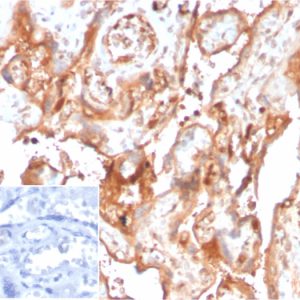

Alpha-2-HS-glycoprotein, Alpha-2-Z-globulin, Ba-alpha-2-glycoprotein, Fetuin-A, 59 kDa bone sialic acid-containing protein; Aa2-066; AHS; A-2-HS-glycoprotein chain B; Alpha-2-Z-globulin; HSGA Asialofetuin; Ba-alpha-2-glycoprotein; BSP; Countertrypin; Fetua; Fetuin A; Glycoprotein PP63